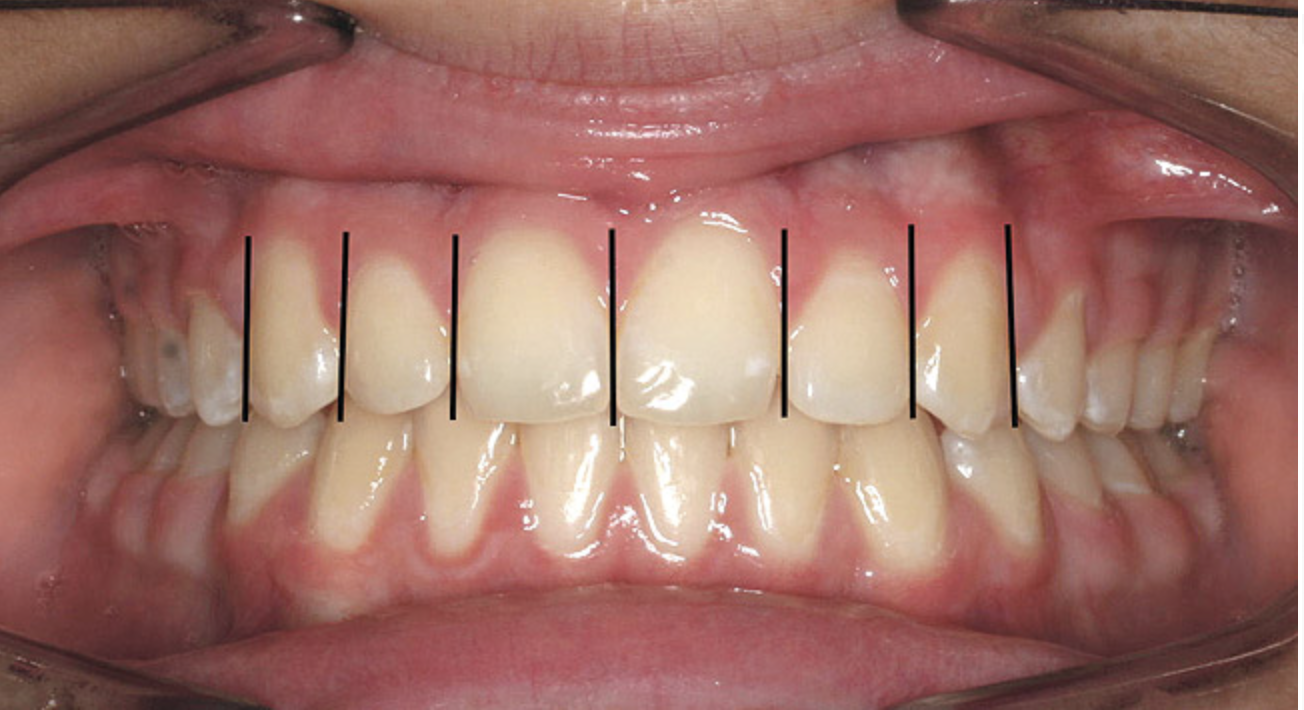

All teeth have a characteristic axial alignment that creates esthetic balance. The restorative dentist can alter the appearance of the inclination by reshaping the tooth or with a restoration (Figure 3). However, orthodontic tooth movement can make significant improvements in axial position on a routine basis. The orthodontist should always attempt to set the alignment to the best advantage for the restorative dentist.

Figure 3  There is a mesial inclination of the maxillary teeth from gingival to occlusal in the esthetic dentition. Maxillary posterior teeth have an axial inclination which converges from the gingival through the occlusal toward a central fulcrum.

Figure 3